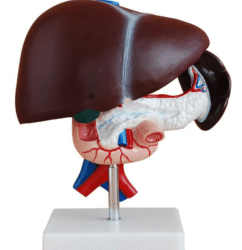

ATL-12 MALE MUSCLES FIGURE 2 PARTS

The model is an anatomically accurate representation of the human anatomy, complete with superficial and deep musculature, the digestive system, lymphatic system, respiratory system, urinary system, circulatory system, endocrine system, and nervous system. Our model has removable organs and dissectible features for a complete educational experience.

Classification:

Skeleton Models(human bone, muscle, etc.)